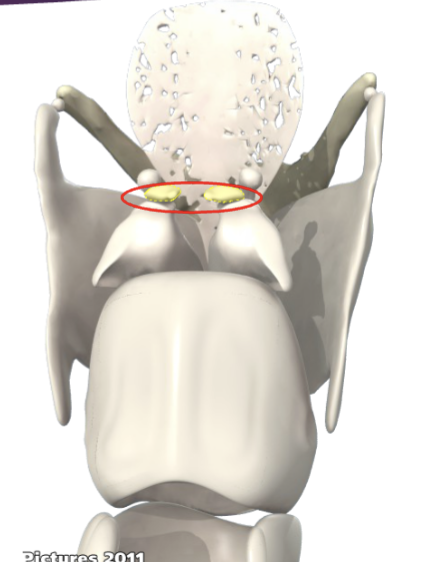

What ligament is this?

Conus elasticus

What ligament is this?

Vocal ligament

What ligament is this?

Posterior cricoarytenoid ligament